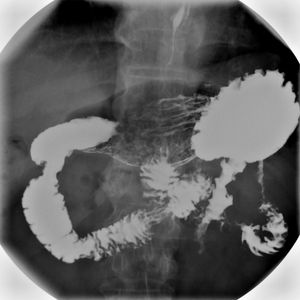

상부위장관조영술은 식도, 위, 십이지장을 검사하는 방법으로, 바륨을 사용하여 X-레이 촬영을 한다. 바륨 삼킴 엑스레이 검사(바륨 식도 조영술), 바륨 식사 검사, 바륨 추적 검사, 장액 주입술, 바륨 관장 검사 등이 있다. 상부위장관조영술은 식도 역류, 연하 곤란, 궤양, 종양 등 다양한 질환을 진단하는 데 사용되며, 소장 조영술은 소장의 형태와 병변을 확인하는 데 활용된다. 검사 결과는 방사선과 의사가 판독하며, 소장 질환, 연하곤란, 크론병, 위식도 역류 질환 등을 평가하는 데 도움을 준다. 검사 전에는 환자 동의가 필요하며, 방사선 노출, 변비, 알레르기 반응 등의 부작용이 발생할 수 있다. 황산바륨은 1910년 의료 조영제로 사용되기 시작했다.

상부 위장관 조영술은 식도, 위, 십이지장을 검사하는 방법이다.

바륨 X-선 검사는 위장관의 여러 부분을 검사하는 데 사용된다. 여기에는 바륨 삼킴 검사, 바륨 식사 검사, 바륨 추적 검사가 있다.[1] 바륨 삼킴 검사, 바륨 식사 검사 및 바륨 추적 검사는 함께 상부 위장관 시리즈(또는 검사)라고도 한다.[2] 상부 위장관 시리즈 검사에서는 황산 바륨을 물과 혼합하여 경구 투여한다.[1]

바륨 엑스레이 검사는 위장관의 외형과 기능을 연구하는 데 유용한 도구이다. 식도 역류, 연하 곤란, 식도열공 헤르니아, 협착, 게실, 유문 협착, 위염, 장염, 염전, 정맥류, 궤양, 종양, 위장관 운동 이상을 진단하고 추적 관찰하는 데 사용되며, 이물질을 감지하는 데에도 사용된다.[2][4] 컴퓨터 단층 촬영, 자기 공명 영상, 초음파 영상, 내시경 검사, 캡슐 내시경과 같은 더 현대적인 기술로 대체되고 있지만,[5] 바륨 조영 영상은 더 저렴하고, 더 널리 사용 가능하며,[6][7] 얕은 점막 병변을 평가하는 데 더 나은 해상도를 제공한다는 장점이 있어 여전히 널리 사용되고 있다.[5][8]